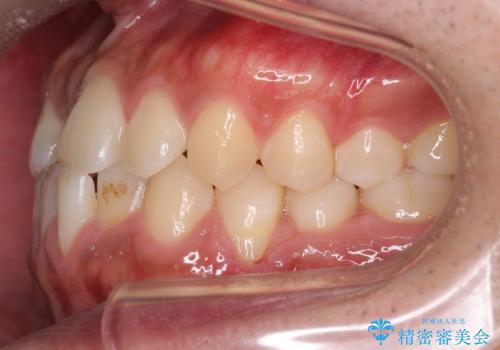

骨格性の受け口の矯正 部分ワイヤーで上の前歯を前に、 マウスピースで下の前歯を後ろに。

前歯のかみ合わせが逆になり上の前歯が奥に入っていました。

骨格性の受け口だったため、矯正用のミニスクリューを用いて、下の前歯をしっかり内側に入れました。

前歯を前に乗り越えさせるのは、ワイヤー矯正が一番早く歯に負担がかかりにくいです。

また、下顎はミニスクリューからマウスピースにゴムをかけて、下の歯並びが前に出ないようにして並べています。